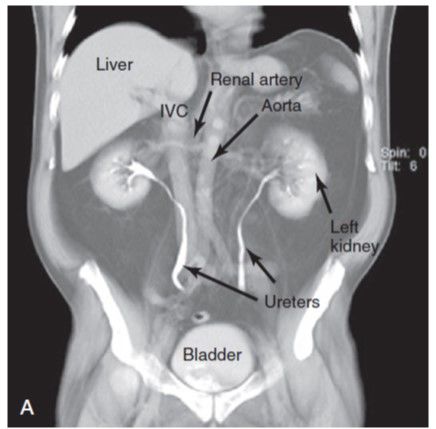

3. RX

1. KUB, SE EXAMINAN CUIDADOSAMENTE

1. Anormalidades del esqueleto, Bordes suaves del tejido hepatico, bazo y psoas, patrones de gas en el intestino y calcificaciones

1. Examinar tamaño renal

1. El riñón izquierdo es un poco superior a l derecho

2. Uréter

1. Anteriores al psoas en L3 y L5